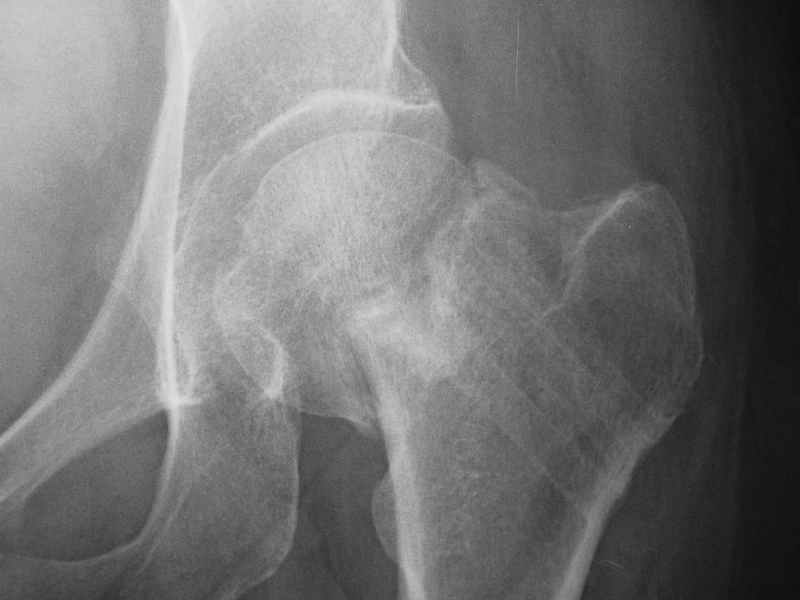

При явно выраженном варусе и флексионных состояниях после сросшихся переломов шейки бедра у молодых рекомендуется реконструктивная операция по исправлению варуса для предотвращения раннего деформирующего артроза, приводящего в результате переднего импинжмента, как показано на снимке.

Межвертельная вальгусная остеотомия представляет наименьший риск среди всех реконструктивных операции в проксимальной части бедра, создавая наилучшие биомеханические условия (увеличивается сила абдукторов, увеличивается сила суставной реакции, уменьшение рычага моментов абдукторов и уменьшение скольжения) и при меньшем риске повреждения кровоснабжения головки, где обычно в 90% случаях достигается отличный результат при применении метода для лечения ложных суставов шейки бедра.

После вальгусных межвертельных операции уже через 2 месяца можно получить результат (predicted outcome), а когда после спонгиозных шурупов результат надо ждать не менее 3-4 месецев, а иногда при свежих переломах сращение в шейке бедра наступает не раньше 5-6 месяцев, тем более при таком варусе спонгиозная фиксация не гарантирует дальнейшее скольжение перелома и ухудшения варуса.